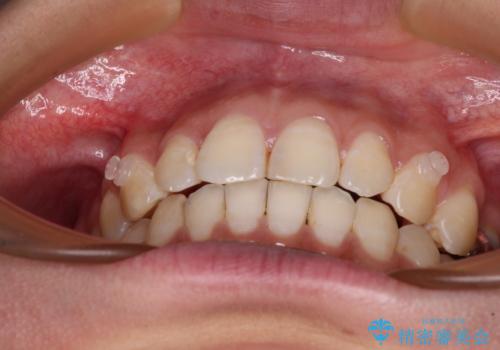

【モニター】隠れている下顎の前歯をインビザラインで改善

- 下顎の前歯が隠れていることと、デコボコを気にして来院された患者様です。

目立ちにくい装置を希望されていたため、ワイヤー装置とインビザラインを提案したところ、インビザラインを希望されました。

銀歯やムシ歯処置の必要な歯が奥歯にあり気になっていたので、矯正治療の途中でセラミッククラウンへ変更し、その後歯列を仕上げていくこととしました。

咬み合わせと目立っていた銀歯が改善され、患者様には大変満足していただきました。